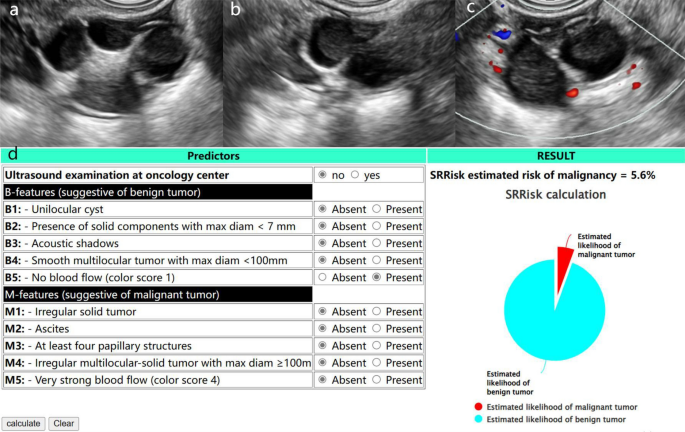

Of these methods, the subjective assessment had the highest diagnostic accuracy and specificity (94.5% and 97.0%, respectively), but was less sensitive than the O-RADS correlation model (86.5% vs. 100%) (Table 4). Of the lesions classified as malignant by O-RADS (v1), 18 benign lesions were successfully downgraded when assessed by combined SRR, and 11 lesions were classified as benign when assessed using O-RADS (v2022) (Figs. 3 and 4).

A 65-year-old woman with a fibroma of the ovary in the left adnexal region. (a) and (b) Longitudinal and transverse section of the lesion, B-mode US showed a smooth solid mass with acoustic shadowing. (c) Small amount of blood flow signal within the lesion (Color Score = 2). (d) Results of SRR assessment of the lesion. Lesions was classified as O-RADS (v1) category 4, O-RADS (v1) combined with SRR assessment and O-RADS (v2022) category 3.